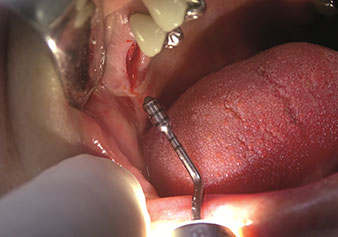

Internal sinus lift

W&H also offers the perfect solution for the internal sinus lift.

Following preparation of the maxillary sinuses with the corresponding instrument set (Fig. 3), the new Z35P instrument (Fig. 4) is used to lift the membrane hydrodynamically. The same instrument set can also be used for piezosurgical preparation of the implant bed in increasing diameters (Figures 3 and 4 included with the kind permission of Dr Mario Kirste, Frankfurt/Oder).